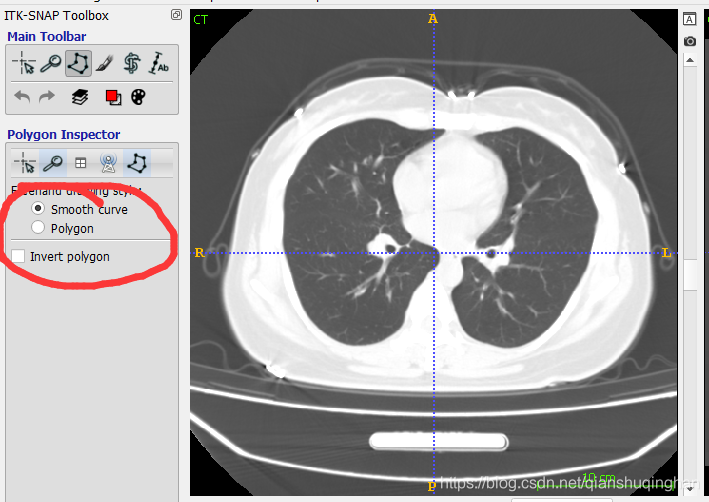

选择勾画工具,分为画刷和画笔两种,左侧为画笔,按住左键勾画闭合轮廓后确认即可填实、得到目标区域;右边为画刷,需要手动完整涂抹目标区域:按住左键涂抹、按住右键擦除。

可选择不同的画笔模式,平滑折线或者间断折线

绘制闭合轮廓:

点击accept